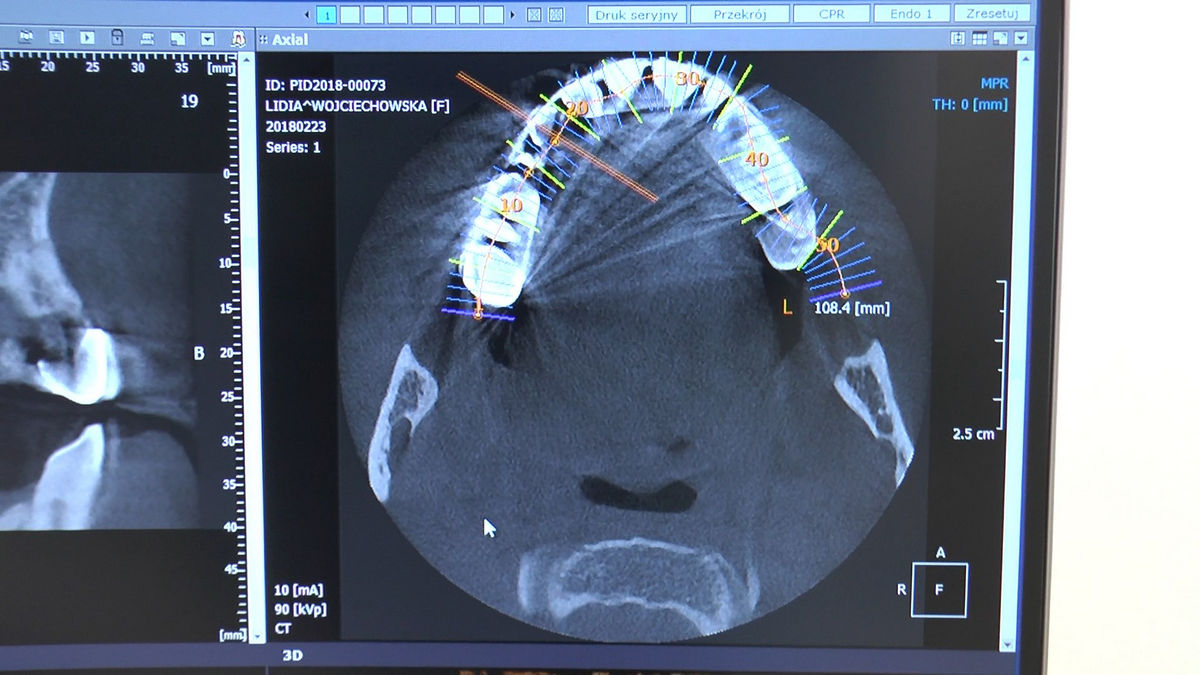

Tuż przed 100 Rocznicą Odzyskania Niepodległości, 9 i 10 listopada 2018 roku, kursanci VI Sezonu Practiculum Implantologii odbyli 7 Sesję. Dwa dni intensywnego szkolenia poświęcone zostały na zabiegi z zakresu chirurgii implantologicznej. Kursanci wykonali szereg zabiegów u Pacjentów pod kierunkiem Mentorów – dr n.med. Violetty Szycik i dr n.med. Magdaleny Kisłowskiej-Syryczyńskiej. Jak zwykle nie zaliczały się one do najłatwiejszych. W większości były przeprowadzone w arcytrudnych warunkach wynikających przede wszystkim ze stanu tkanki kostnej oraz stanu zdrowia, co wymagało precyzyjnego planowania. Z zabiegów skorzystało 17 Pacjentów, także z zastosowaniem znieczulenia ogólnego w formie sedacji dożylnej. Wszczepiono 23 implanty, wykonano zabiegi natychmiastowej implantacji po mnogich ekstrakcjach, przeprowadzono zabiegi augmentacji oraz 3 zabiegi sinus lift z zastosowaniem preparatów kościozastępczych i PRF. Wszystkie zabiegi przeprowadzane zostały zgodnie z planem i dużym stopniem samodzielności, który odpowiada zakresowi poszerzających się umiejętności szkolących się lekarzy. W panelu edukacyjnym Sukces Twojego Biznesu odbyły się pierwsze zajęcia z NLP. Kolejna 8 sesja już na początku grudnia.